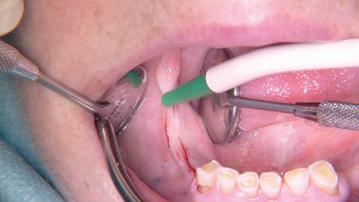

• Chirurgie parodontale

• Mise en pratique de la piezochirurgie.

• Réalisation d’extractions atraumatiques : sauvegarde du capital osseux disponible.